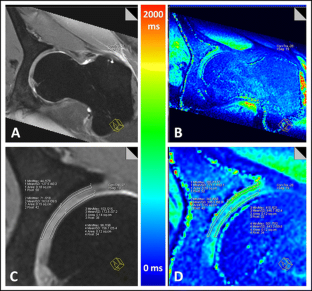

Fig. 4